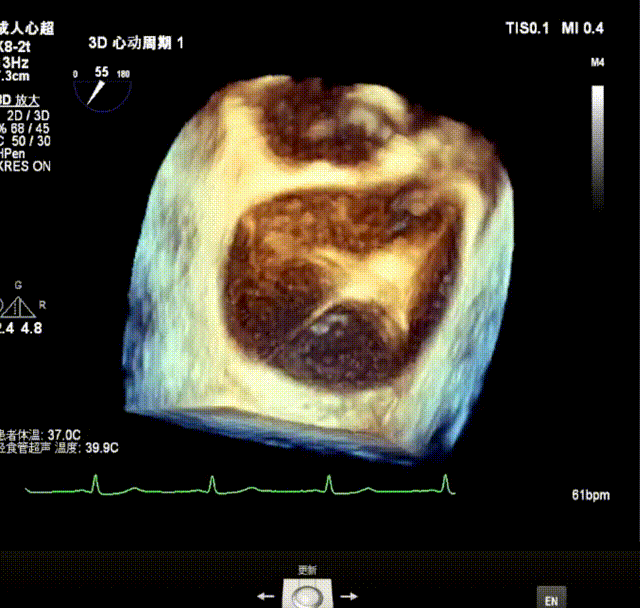

3D enface view示二尖瓣P2P3区瓣叶脱垂,偏心性返流

3D测量二尖瓣瓣口面积4.50cm² 病变宽度为1.79cm